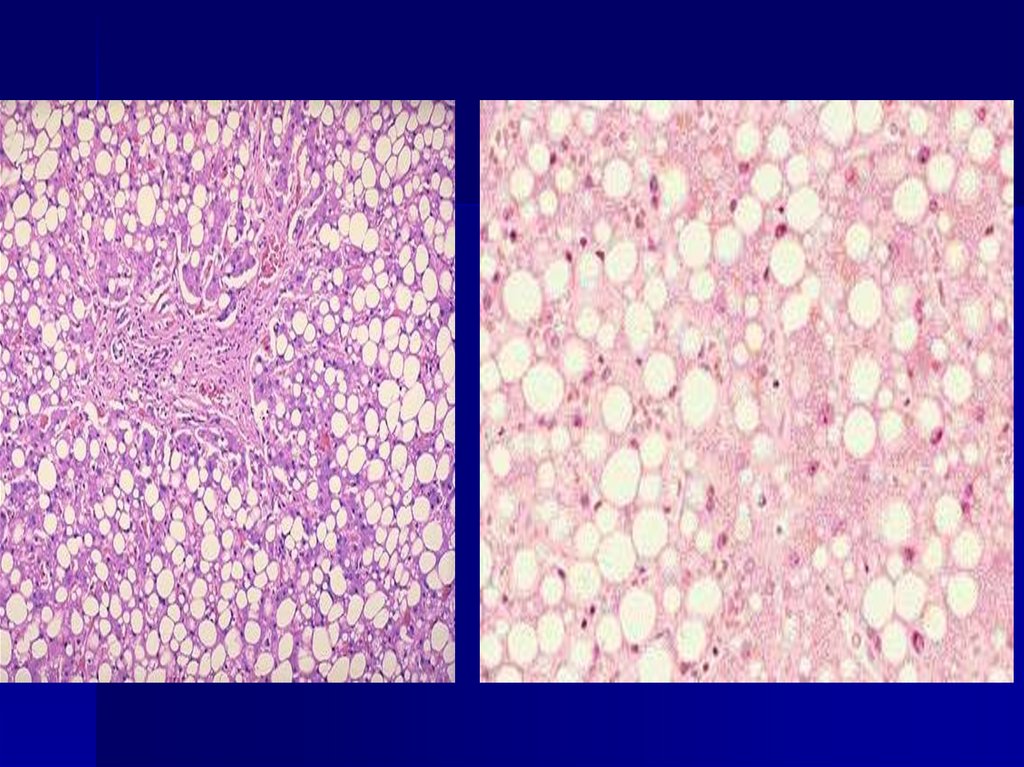

Паренхиматозная жировая

Окрашивание гемотоксилин-эозином

Окрашивание Судан-ІІІ

Внешний вид печени:

Увеличена, дряблая,

желто-коричневого

цвета. При разрезе на

лезвии ножа и

поверхности виден

налет жира.